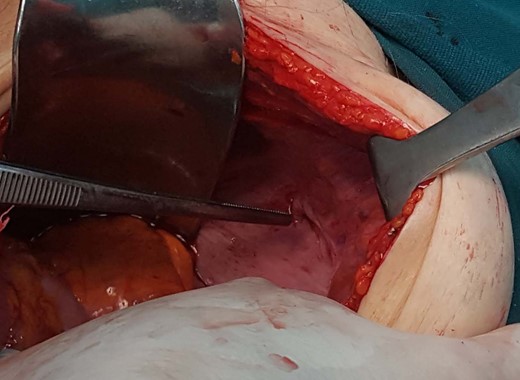

The patient, was admitted to the hospital’s emergency department with a 24-h evolution of diffuse abdominal pain and progressive abdominal distension, associated with persistent vomiting and irradiating pain to the right leg. Patient had a previous history of abdominal surgery including laparoscopic cholecystectomy and repair of umbilical hernia, as well. Physical examination revealed an under-weight female, with distended and tympanitic abdomen, hyperactive bowel sounds with audible rushes associated with vigorous peristalsis, diffuse abdominal pain to deep palpation and no signs of peritoneal irritation or inguino-abdominal hernias. There were neither faeces nor intraluminal mass or blood on the digital rectal examination. Besides, Howship–Romberg sign was negative. The patient maintained her haemodynamic and ventilatory stability. Naso-gastric tube drained ~300 mL of fecaloid fluid. Laboratory exams showed leukocytosis (14 280–70.01% neutrophils) and an increased C-reactive protein level (4.3 mg/L). Upright radiographs demonstrate multiple, short air-fluids levels. Based on the suspicion of an acute bowel obstruction a CT of the abdomen and pelvis was the best applicable solution. The CT scan identified a small intestine segment strangulated through the right obturator foramen and an intestinal distension proximally (Fig. 1). Soon after, the patient underwent an emergent infraumbilical midline laparotomy that confirmed the diagnosis; right obturator hernia with ileal partial wall strangulation (Richter’s type). This was gently released and found to be congested although still viable. Once the bowel loop was released and subjected to warm packs, the colour returned to normal. The obturator hernia defect was roughly 1 × 1 cm2 and this was closed using a single stitch of absorbable polyglactin no. 2 suture (Fig. 2). No other pathology was found. Mass closure of laparotomy wound was with loop polydioxanone (PDS) suture and clips to close the skin. The patient remained stable postoperatively over the course of her hospitalization. She tolerated an oral diet on the second and was discharged on the fourth postoperative day respectively, with an uneventful postoperative recovery.